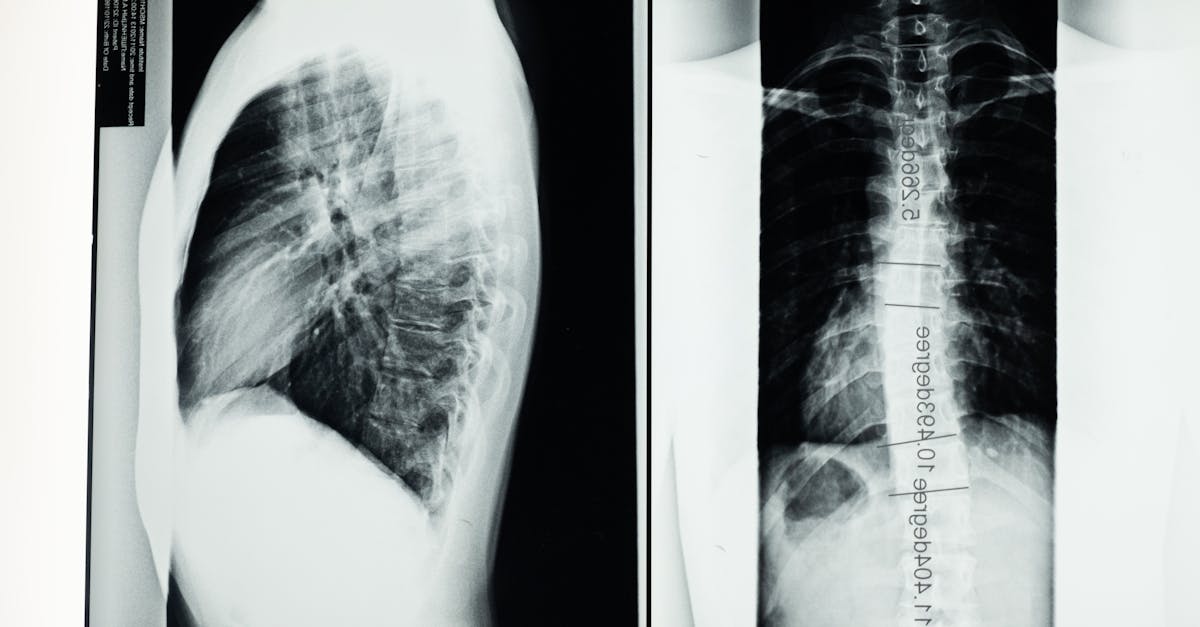

Navigating the daily challenges of scoliosis can feel overwhelming. This condition, marked by an abnormal curvature of the spine, often leads to discomfort and can significantly impact day-to-day activities. Fortunately, Pulse Align offers a holistic approach that utilizes neuromuscular health techniques to improve posture and promote natural balance. This article explores how small, gentle adjustments can lead to big relief, emphasizing the importance of posture exercises and mindful movement.

Understanding the Impact of Scoliosis on Your Posture

For many individuals living with scoliosis, challenges such as bad posture, kyphosis, and lordosis are common. These conditions often result from compensatory mechanisms in the body attempting to manage the curvature of the spine, leading to symptoms like forward head posture and rounded shoulders. By cultivating an awareness of how scoliosis affects the body, individuals can actively engage with strategies designed to realign and maintain proper sitting posture.

Postural imbalance involves poor load distribution and is often reversible, while scoliosis is a structural deformity of the spine.